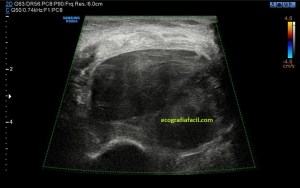

En la imagen 3 puedes ver un menisco que en su parte central tiene una línea hipoecogénica, bastante sutil, fíjate bien, irregular que lo divide en 2 partes. Pero ¿qué pasa cuando un menisco está dañado? Cuando un menisco por sobreuso, sobrepeso o la razón que sea pueden mostrar cambios en la ecoestructura, ya sea por que se han fisurado, como el de la imagen 2, incluso pueden llegar a romperse. Es fisura o rotura puede ser la vía de escape del líquido intraarticular de la rodilla hacia la parte extraarticular y si eso se produce, podemos encontrarnos con esto:

4

El líquido ya se ha salido y ha formado una bolsa situada superficial al menisco, profundo al ligamento colateral y que está señalado con flecha amarilla. Marcadamente anecoico puedes verlo en tamaños variables en función el alcance del líquido que haya salido y en función de las variantes propias de cada paciente.

La presentación de éste era así:

5

Semiológicamente ves una ecoestructura anecoica con septos hiperecogénicos paralelos en alguna porción del quiste que no muestra vascularización. Este estaba en torno a los 2,5 cms, en el momento de la exploración.